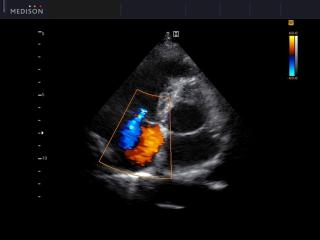

Heart (4 chamber view), color doppler

MySono-U5. Heart (4 chamber view), color doppler.